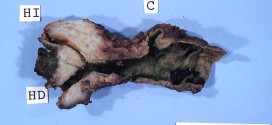

El adenocarcinoma de las vías biliares. El sistema para drenar la bilis, incluye los conductos o vías extrahepático, conductos biliares intra y la vesícula biliar. Son como una red de cañerías, llamados conductos que están conectados con la vesícula biliar, el intestino delgado y el hígado. Es una enfermedad por la cual se forman células malignas cancerosas en los tejidos …

El adenocarcinoma de la vesícula biliar. Es una enfermedad por la cual se forman células malignas cancerosas en los tejidos de la vesícula biliar es una enfermedad poco frecuente por la que se encuentran células cancerosas en los tejidos de la vesícula biliar. La vesícula se localiza en la fosa vesicular, en la cara inferior del hígado. Por lo general …